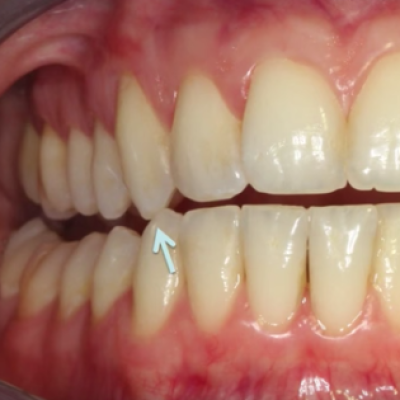

Canine Tooth Guidance

Our canine teeth play an essential role in guiding our jaws side to side to prevent excessive wear and fracturing of our other teeth. Molars are very strong in the up-and down biting movement during everyday eating and chewing, but NOT with lateral(side to side) movements. The tips of our...

Treatment for tooth wear

Due to the effect of tooth wear, some degree of enamel loss is always present. We follow the concept of minimally invasive treatment which means we preserve as much of your tooth structure as possible and aim to just adding 'enamel' back to the tooth. In essence you have...